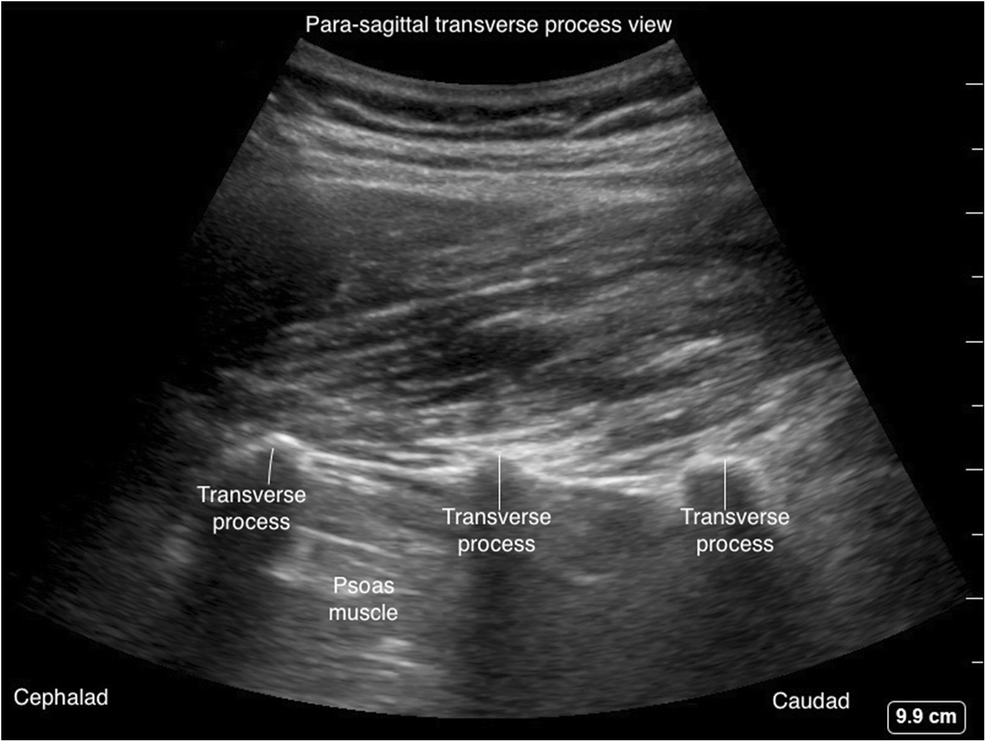

Парасагиттальный вид поперечного отростка

Ультразвуковой датчик располагают в парасагиттальной плоскости на несколько сантиметров латеральнее средней линии, как показано на рис. 4, положение датчика А и рис. 6. Поверхность поперечных отростков видна в виде круглых гиперэхогенных контуров с более глубокими гипоэхогенными тенями в виде темных пятен. пальцевидные выступы, как показано на рис. 7. Это описывается как «знак трезубца». Между этими гипоэхогенными тенями видна большая поясничная мышца.

Рис. Положение датчика для парасагиттального сканирования в поперечном отростке.

Рис. Парасагиттальный поперечный отросток (знак трезубца).

Парасагиттальное сканирование может быть использовано для определения точного уровня позвоночника перед процедурой.